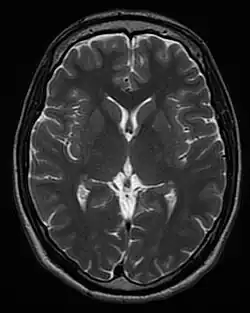

| T2 weighted | T2 | Measuring spin–spin relaxation by using long TR and TE times |

Standard foundation and comparison for other sequences |

Each tissue returns to its equilibrium state after excitation by the independent relaxation processes of T1 (spin-lattice; that is, magnetization in the same direction as the static magnetic field) and T2 (spin-spin; transverse to the static magnetic field). To create a T1-weighted image, magnetization is allowed to recover before measuring the MR signal by changing the repetition time (TR). This image weighting is useful for assessing the cerebral cortex, identifying fatty tissue, characterizing focal liver lesions, and in general, obtaining morphological information, as well as for post-contrast imaging. To create a T2-weighted image, magnetization is allowed to decay before measuring the MR signal by changing the echo time (TE). This image weighting is useful for detecting edema and inflammation, revealing white matter lesions, and assessing zonal anatomy in the prostate and uterus.